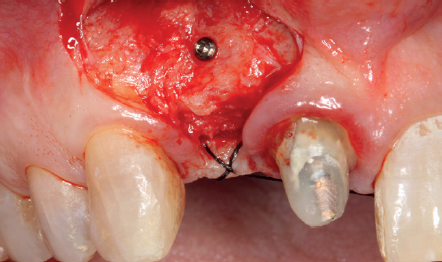

(Figuras 5 y 6). Con esta imagen se procede a la apertura de un colgajo y la explantación del implante. Se retira también la corona situada en el diente 1.1 para poder realizar otra corona que servirá para apoyar el provisional en extensión para la zona del 1.2, mientras cicatriza la primera intervención. En este primer abordaje se coloca también un injerto en bloque obtenido de la rama mandibular que se fija con un microtornillo en la zona a regenerar donde se ha perdido la cortical vestibular. Una vez fijado y posicionado, se rellena alrededor del injerto en bloque con hueso particulado obtenido con un bone-scraper de la misma zona donante embebido en PRGF-Endoret para una mejor fijación y viabilidad celular (Figuras 7-9).